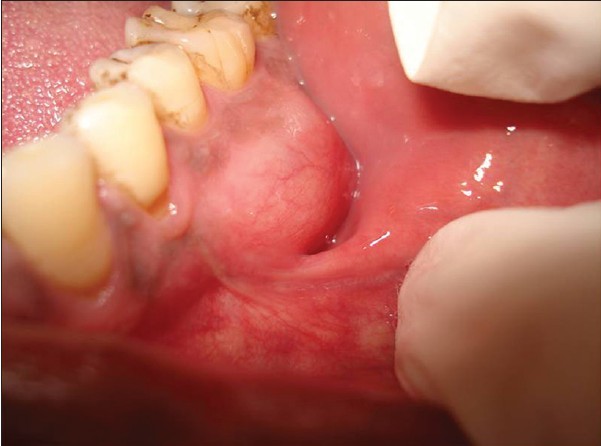

How pariod tumors affect oral health

Parotid tumors are abnormal growths of cells (tumors) that form in the parotid glands. The parotid glands are two salivary glands that sit just in front of the ears on each side of the face. Salivary glands produce saliva to aid in chewing and digesting food.

There are many salivary glands in the lips, cheeks, mouth and throat. Tumors can occur in any of these glands, but the parotid glands are the most common location for salivary gland tumors. Most parotid tumors are noncancerous (benign), though some tumors can become cancerous.

Parotid tumors often cause swelling in the face or jaw that usually isn't painful. Other symptoms include numbness, burning or prickling sensations in the face, or a loss of facial movement.